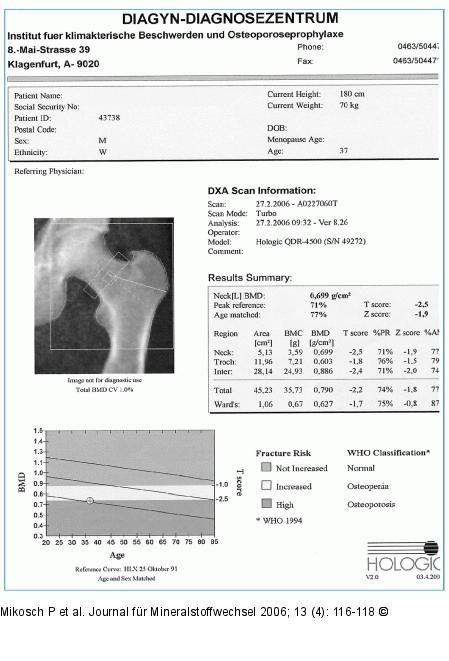

Abbildung 5: DXA-Scan - Femur